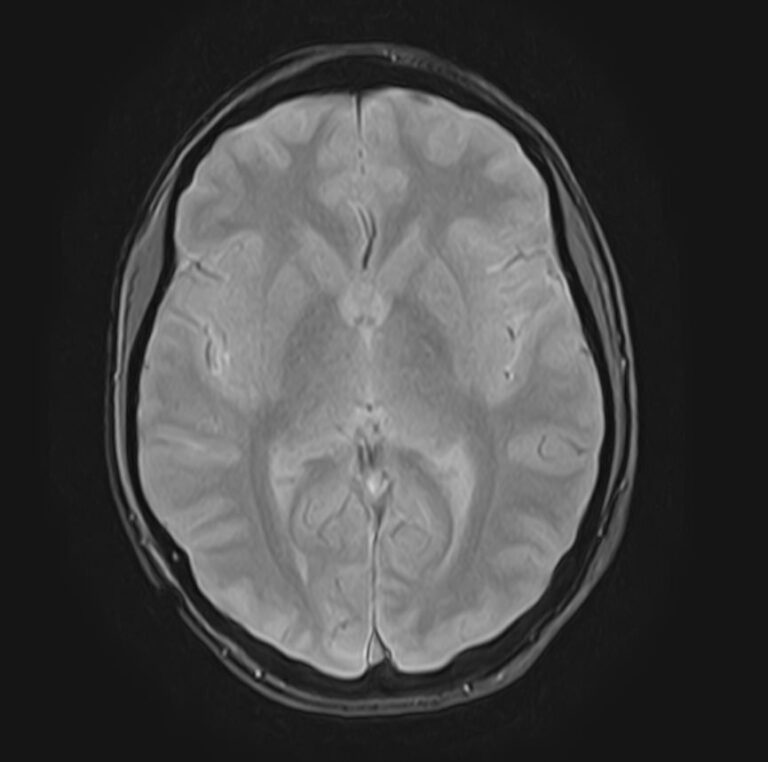

В нашей клинике мы проводим комплексное исследование, включающее МРТ головного мозга и всех отделов позвоночника. Методика комплексного обследования применяется при наличии у пациента сочетанных поражений головного мозга, спинного мозга и позвоночного столба.

Стандартная МРТ головного мозга дает важную информацию о состоянии и структуре мозговой ткани для выявления большого числа заболеваний, в том числе опухолевых образований, демиелинизирующих заболеваний, воспалительных процессов головного мозга и мозговых оболочек.

При подозрении на распространенный процесс с поражением различных уровней позвоночника целесообразно проведение МРТ для диагностики дегенеративно-дистрофических заболеваний, травматических, воспалительных изменений, а также опухолевых процессов позвоночника. Метод позволяет оценить состояние структур позвонков, позвоночного канала с расположенным в нем спинным мозгом и окружающих мягких тканей, кроме того, является основным способом диагностики демиелинизирующих заболеваний спинного мозга.

Исследование проводится на современном томографе TOSHIBA VANTAGE TITAN 1,5 Тесла. За счет высокой индукции магнитного поля аппарат обладает  высокой разрешающей способностью, что позволяет проводить точную диагностику заболеваний центральной нервной системы и позвоночника.